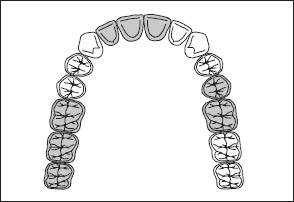

• Kennedy Class I arch: Characterized by bilateral edentulous areas located posterior to the remaining natural teeth (Figs 1-11 and 1-12).

Fig 1-11 Maxillary Kennedy Class I arch.

Fig 1-12 Mandibular Kennedy Class I arch.